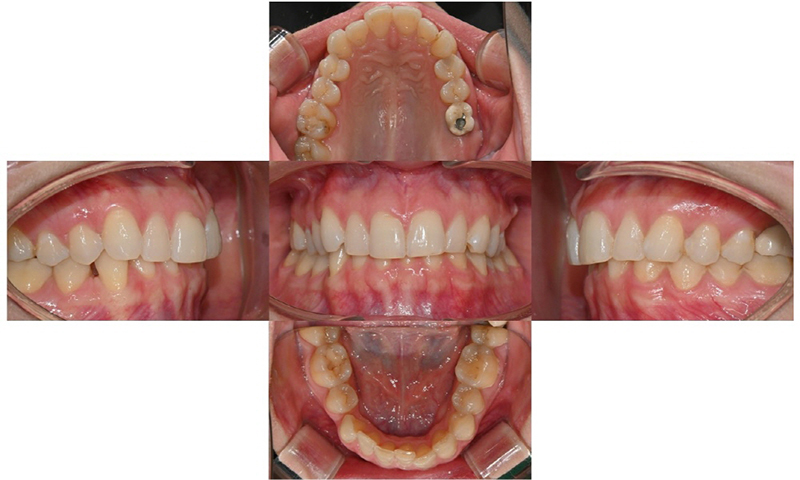

Her smile already had a beautiful smile arc—the curve connecting her upper front teeth followed the contour of her lower lip perfectly. She was satisfied with her overall appearance, but wanted to correct the slight size difference and minor misalignment between her two front teeth to make them look more even.

Upon examination, her left central incisor was slightly larger than the right, and there was mild crowding in both upper and lower anterior teeth. She had previously undergone extraction orthodontics—her lower first premolars had been removed, leaving a small gap on the right side. In addition, due to deep overbite, her lower front teeth were barely visible. She also had a dental implant on her lower left first molar, while the second molar was missing.